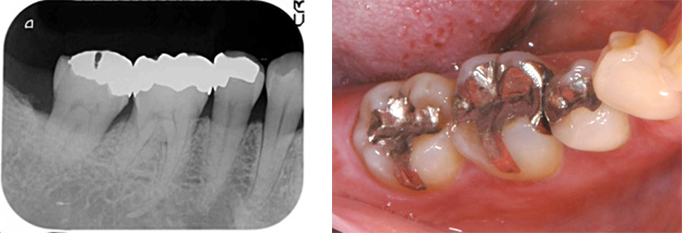

日本人の場合は特に噛み合せの問題や不適切な歯科治療、あるいはそれらの複合的要因の結果によって歯を失われる方がとても多く見られます。

向かって右奥歯の根が露出してしまっています。

噛み合わせや不適切な治療や歯ブラシの仕方によって、歯周病が進行しきった状態です。

こうなってしまうと残念ながら救う手だてはありません。

前方の歯の詰め物、被せ物も決して精度高い治療とは言えません。歯周病は早期発見・早期治療が大切なのです。